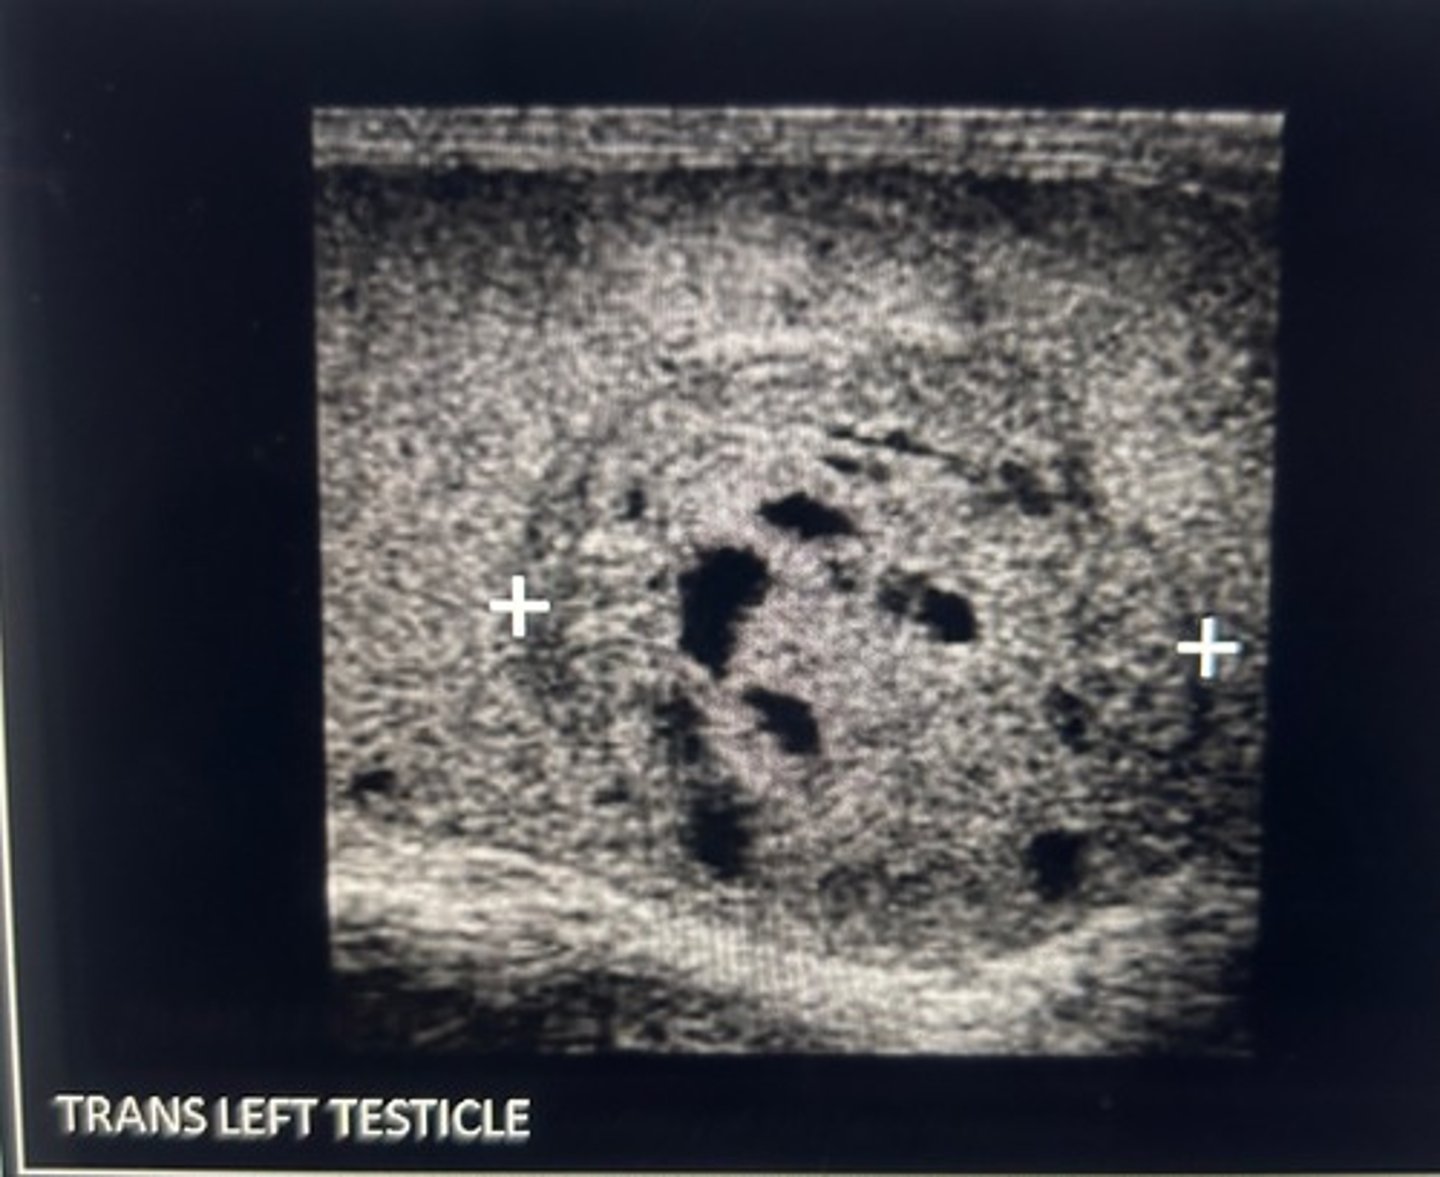

A 3 cm hypoechoic mass is identified in the right testicle. The radiologist request that you perform an abdominal ultrasound. What are you looking for?

Periaortic lymphadenopathy

The first location at a seminoma spreads is to the retroperitoneal lymph nodes. The right gonadal vein connects directly to the IVC so the renal vein would most likely be unaffected by tumor invasion.